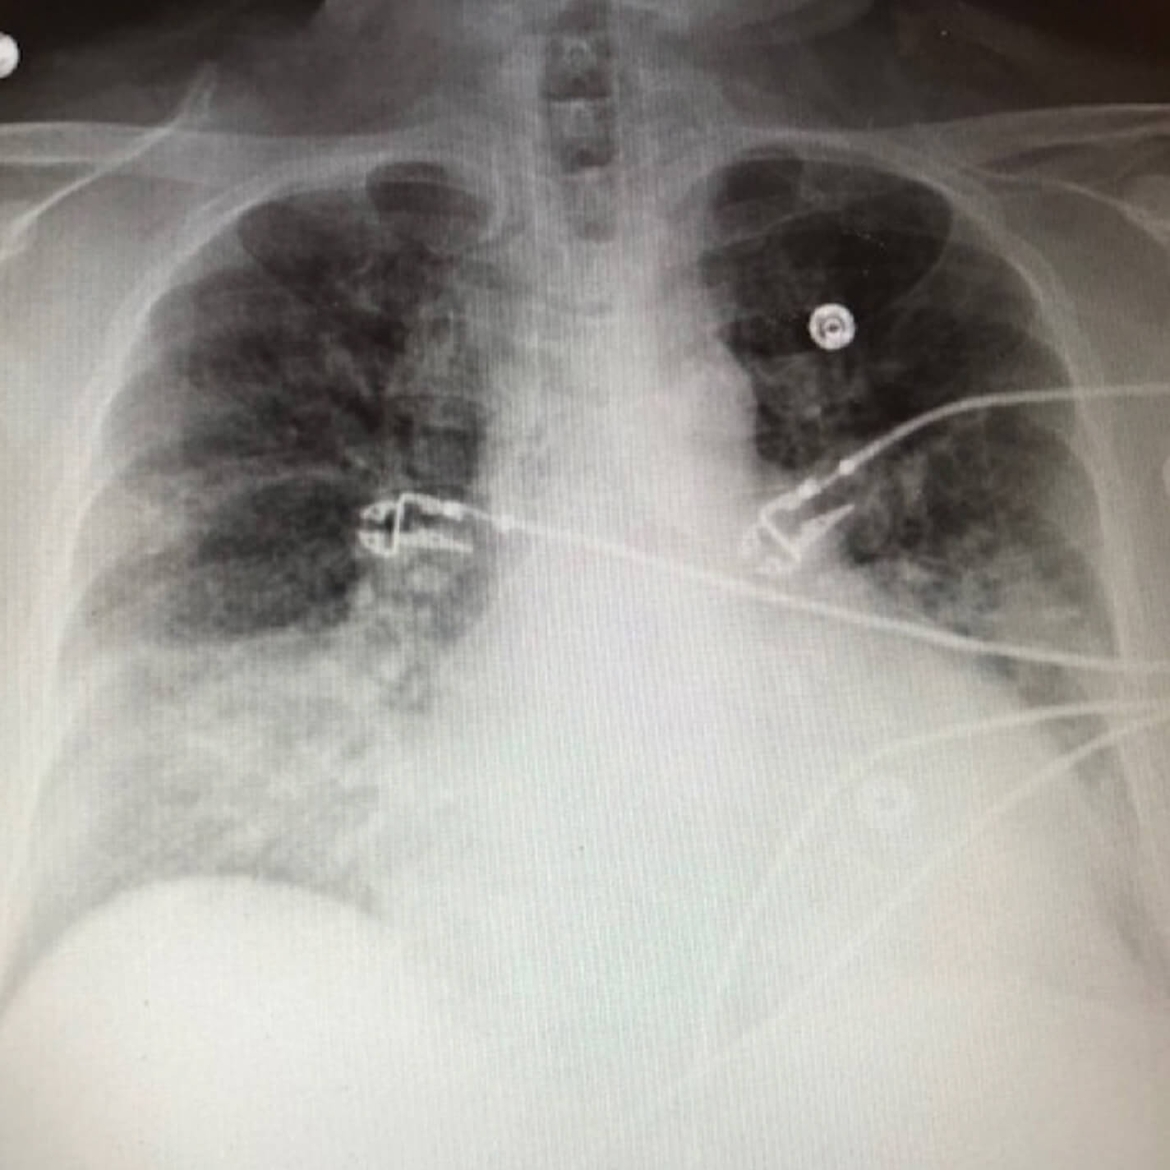

Клиническое излечение* после одного курса лечения с переходом с внутривенного на пероральный приём NUZYRA — повторная госпитализация не потребовалась¹

Контрольная рентгенография грудной клетки (через 2